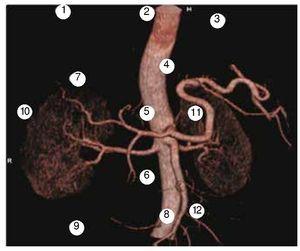

Hay situaciones en el cual el CHC es irrigado por arterias colaterales extrahepáticas, incluso cuando la arteria hepática es patente y esto interfiere con el control eficaz del tumor con QEIA2. Por ende, es importante que radiólogos intervencionistas estén familiarizados con la gama de colaterales extrahepáticas que pueden existir (fig. 6), y los factores que conducen a su formación, y su apariencia en la tomografía computarizada (TC) y angiografía convencional, para poder dar un tratamiento óptimo y prevenir complicaciones. Se han hecho investigaciones sobre la QEIA selectiva a través de la arteria frénica inferior, demostrándose buena respuesta de los tumores3.

Figura 6. Arterias suplementarias potenciales según la localización del tumor. 1: mamaria interna, 2: pericardiofrénica, 3: músculo frénica, 4: frénica inferior, 5: adrenal superior, 6: capsular inferior, 7: capsular superior, 8: omental, 9: cólica, 10: intercostal, 11: gástrica izquierda, 12: gastroepiplóica.

Las arterias colaterales más comúnmente involucradas son la frénica inferior como en el caso de nuestro paciente, las arterias mamarias e intercostales internas. Otras son la rama omental, la arteria suprarrenal, la arteria cística, la arteria renal y la renal capsular, la arteria gástrica y lumbar, y ramas de la mesentérica superior. El contacto directo o invasión en otros órganos, incluyendo estómago, colon, glándula suprarrenal y riñón, pueden crear suministro de sangre al tumor a partir de estos órganos4.